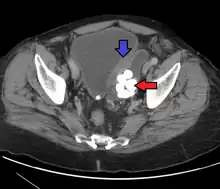

| Transitional cell carcinoma | |

| Other names | Urothelial carcinoma |

| Histopathology of transitional carcinoma of the urinary bladder. Transurethral biopsy. Hematoxylin and eosin stain. | |

Transitional cell carcinoma, also called urothelial carcinoma, is a type of cancer that typically occurs in the urinary system. It is the most common type of bladder cancer and cancer of the ureter, urethra, and urachus. Symptoms of urothelial carcinoma in the bladder include hematuria (blood in the urine). Diagnosis includes urine analysis and imaging of the urinary tract (cystoscopy). Transitional cell carcinomas arise from the transitional epithelium, a tissue lining the inner surface of these hollow organs.[1] When the term "urothelial" is used, it specifically refers to a carcinoma of the urothelium, meaning a transitional cell carcinomas of the urinary system.